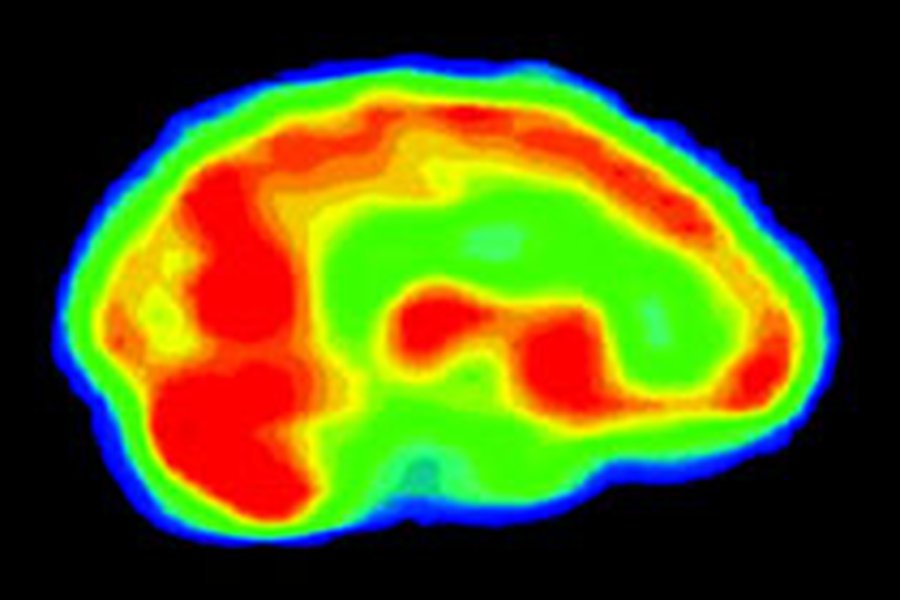

Гомосексуальные наклонности у мужчин и женщин связаны с врожденными особенностями отделов мозга, отвечающих за эмоциональные реакции и агрессию. :::К такому выводу пришли шведские ученые в результате сравнительного изучения результатов МРТ –обследований геев, лесбиянок и лиц гетеросексуальной ориентации.

Обследование на магнитно-резонансном томографе подтвердило известные данные о том, что у лесбиянок и мужчин-гетеросексуалов правое полушарие несколько превышает по объему левое, тогда как у женщин обычной ориентации и гомосексуалистов размеры полушарий были приблизительно одинаковы.

После этого ученые применили метод позитронно-эмиссионной томографии, позволяющей наблюдать изменения активности различных зон мозга в режиме реального времени. Они сосредоточили внимание на миндалевидных телах – группах нейронов внутри височных долей, участвующих в формировании эмоций и связанных с агрессивным поведением.

Как выяснилось, у женщин гетеросексуальной ориентации и мужчин-гомосексуалистов вместе с миндалевидным телом активизировались зоны мозга, которые принято связывать с тревожностью, депрессией и фобиями. В то же время у мужчин-гетеросексуалов и лесбиянок к миндалевидному телу «подключались» отделы, отвечающие за сенсорно-моторные функции, что связано с быстрой и деятельной реакцией на угрожающую опасность.

Как поясняет автор исследования Иванка Савич (Ivanka Savic), полученные данные свидетельствуют о том, что мозг гомосексуалистов и лесбиянок в определенных ситуациях работает по модели, характерной для лиц противоположного пола. Этим, в частности, может объясняться большая подверженность геев к депрессии – расстройству, которое в целом чаще развивается у женщин.